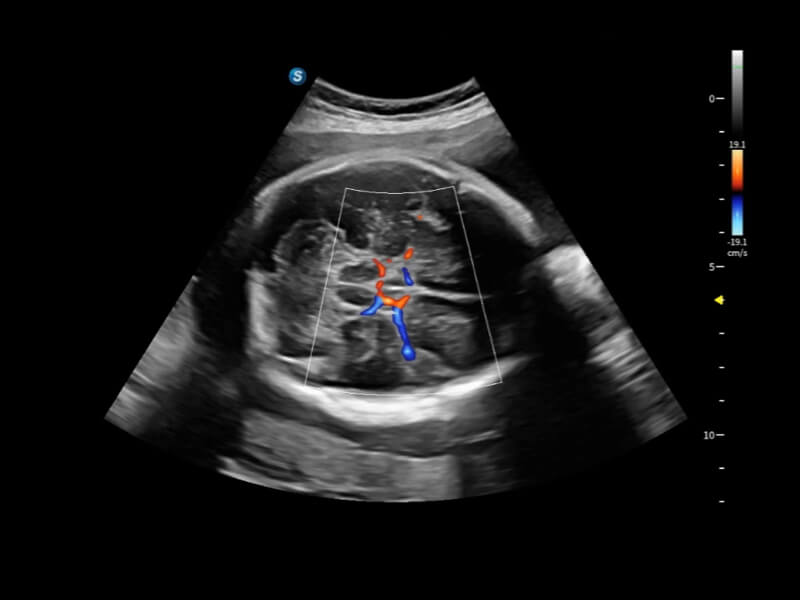

豐富的血流動(dòng)力學(xué)檢測(cè)技術(shù),可在不同醫(yī)療場(chǎng)景中高效捕捉血流信號(hào),助力臨床診療。

在傳統(tǒng)血流的基礎(chǔ)上優(yōu)化掃查和算法策略,能夠更好的抑制組織信息,提煉紅細(xì)胞運(yùn)動(dòng)信息,得到更高幀頻,高靈敏度和分辨率的血流信號(hào),還原更真實(shí)的血流動(dòng)力學(xué)。